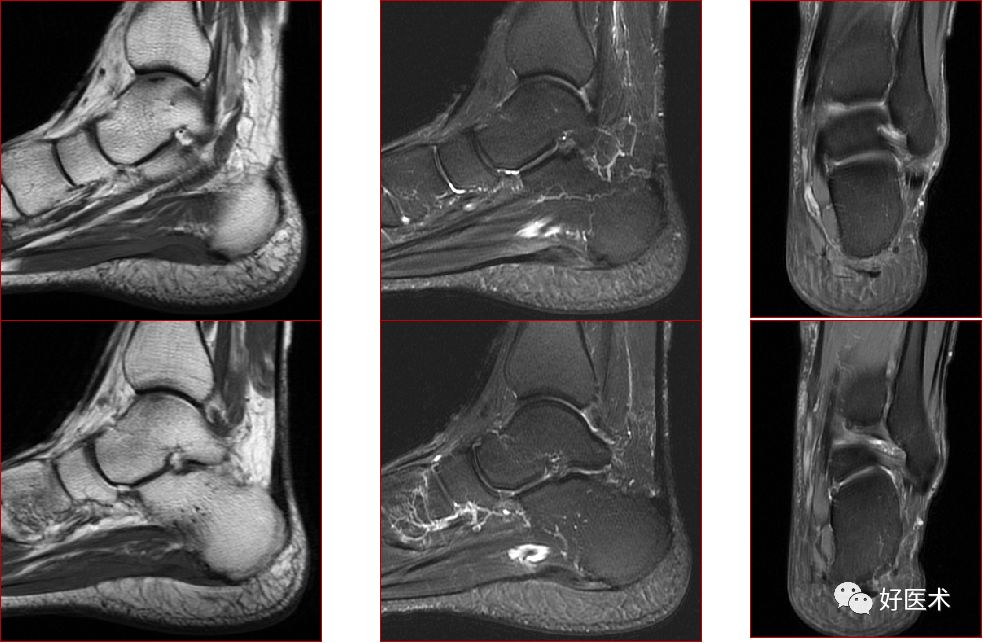

二、软骨病变

chondromalacia 软骨软化分级

1级 浅表病变,软骨变软

2级 浅表病变累及软骨深度约50%

3级 软骨病变累及软骨深度>50%,但未达软骨下骨

4级 软骨破坏并累及软骨下骨